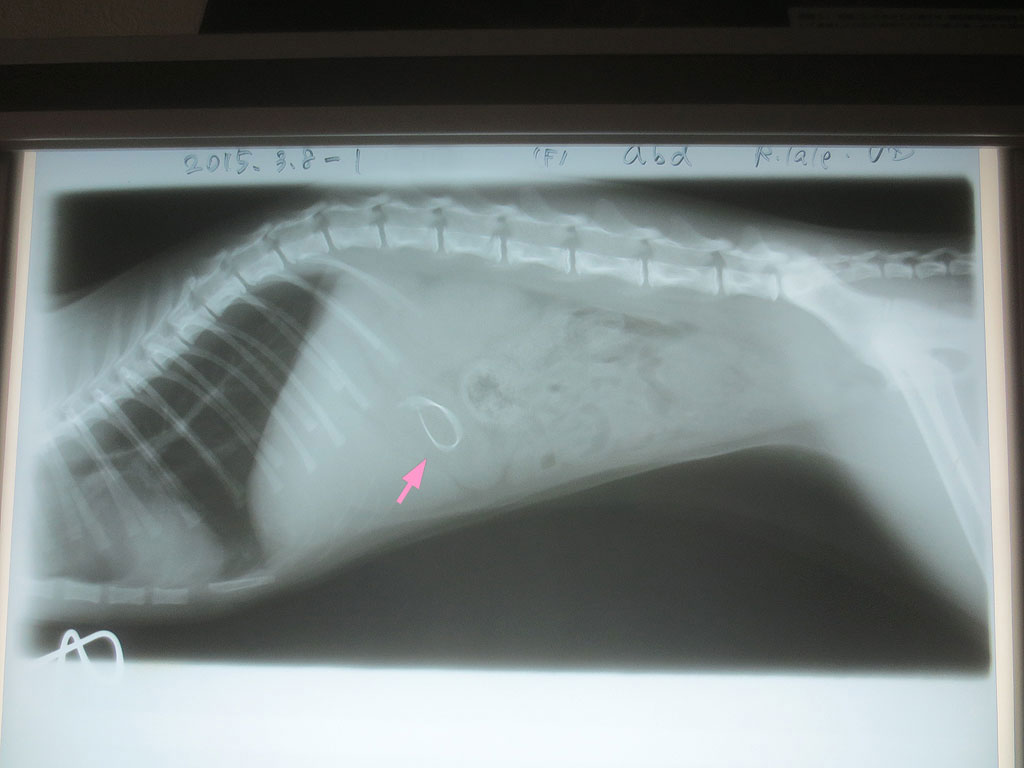

そして、レントゲン写真の現像が終わって、その写真を見させて頂いたのですが、これは前回のレントゲン写真…、前にもアップしたのですが、胃の中に異物があって、これが移動していたかどうかなのですが…。

これが今回の写真…、ちょっと写真の撮り方が悪くって見にくいのですが、残念ながら異物は動いておらず…。